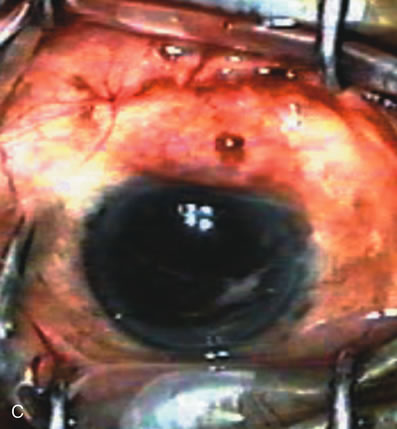

Fig. 5. Anterior chamber angle changes associated with lens extraction and PCIOL This 65-year-old Vietnamese woman has a long-standing history of chronic angle-closure glaucoma treated with laser peripheral iridectomy. The optic nerve demonstrated mild glaucomatous damage and IOP was moderately controlled on two antiglaucoma medications. The cataract was removed through temporal clear corneal phacoemulsification with foldable acrylic IOL. A. Symptomatic cataract in narrow-angle glaucoma eye with patent iridectomy. B. Intraoperative goniophotograph showing crowding of angle with increasing narrowness due to phacomorphic component. C. Intraoperative photograph showing temporal clear corneal approach with IOL in the capsular bag. D. Intraoperative goniophotograph demonstrating deepening of chamber angle following lens extraction. Proposed theories for IOP reduction following lens extraction with complete wound closure:

1. Anterior chamber deepening with improved access to trabecular meshwork

2. Increase in traction on the trabecular meshwork

3. Improved outflow facility mediated by an increase in prostaglandin release

4. Reduction in aqueous humor production

5. Atrophy of ciliary body processes

6. Goniosynechialysis due to intraoperative over deepening of AC with viscoelastic

7. Relief of undiagnosed pupil block